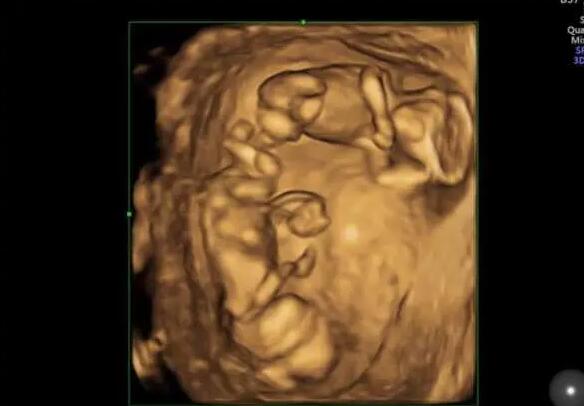

试管婴儿的成功率并不取决于卵泡的数量,而是取决于卵泡的质量。因此,卵泡数量少不要太担心,临沂市人民医院做试管婴儿的成功率是相对较高的,临沂市人民医院做试管婴儿的成功率具体如下:

1.临沂市人民医院生殖科每年有近10万名不孕不育症患者接受治疗,完成新鲜、解冻周期超过10000个,总成功率约为53%-55%。在该医院做试管婴儿取卵只有两个卵子,如果两个卵泡的质量较好,即使只有两个卵泡,成功率也相对较高,可以达到50%左右;

2.但是如果卵泡质量不好,成功率会稍微低一些,可能只有30%-40%;

以上就是“2022临沂市人民医院试管婴儿成功率一览,取卵只有2个能成功吗?”的全部内容了,事实上,做试管婴儿并不是卵泡越多越好,即使卵泡的数量再多,质量不好,也是徒劳的。